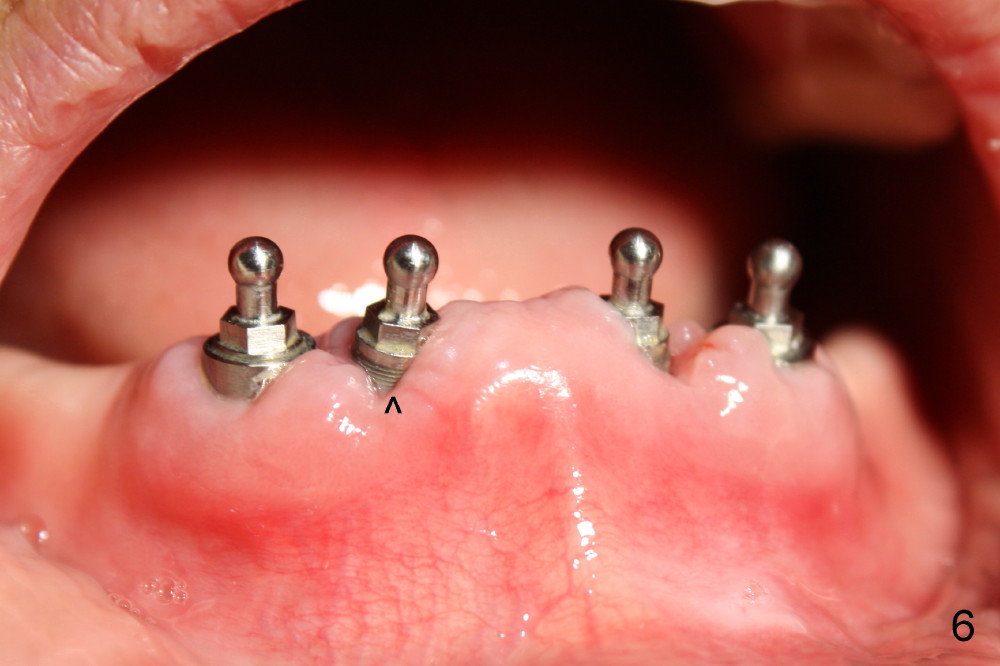

Following tooth extraction, the sockets are thoroughly debrided and packed with Clindamycin gauze (Fig.1: #22,23,26,27). PA is taken when 1.5 mm pilot drills are placed in the lateral incisor sockets and 2.0 mm in the canine sockets (Fig.2). Fig.3 shows that 4.5x17 mm tap (T) is placed in the lower right canine region, while 3.5x17 mm one piece implant is placed in the lower right lateral.